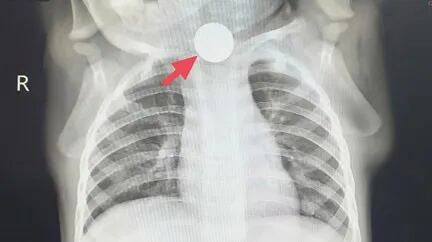

“医生,

孩子一周没好好吃饭了,

就靠喝奶续命,

吃了健胃药也没用啊!”

日前,

上海复旦大学附属儿科医院消化科门诊,

一对父母抱着一岁的宝宝冬冬(化名),

满脸焦急地求助。